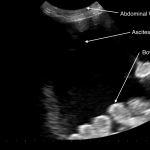

ABDOMINAL ULTRASOUND

Key features of ascites seen in this imaging modality are:

- Anechoic nature: ascites will allow sound waves to pass through it, so it will appear black/dark on ultrasound.

The gallery below organizes examples of how ascites will appear on abdominal ultrasound. Click on the thumbnails below to open up the gallery: